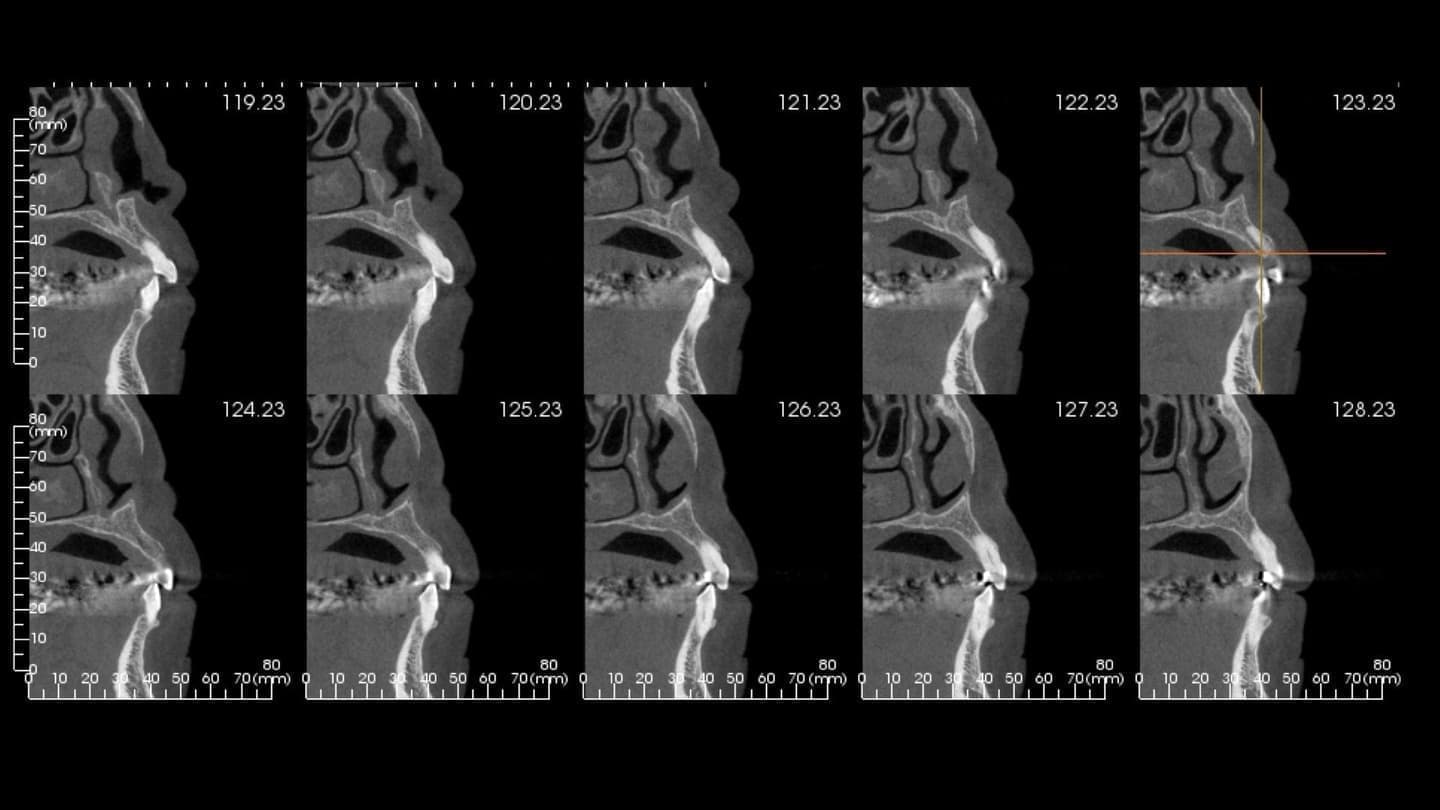

CT

CT(三次元立体画像撮影装置)

国内では数%の歯科医院にしか導入されてません。

CTとは、従来の平面的(2次元)なレントゲン写真を立体的(3次元)に見ることができる装置で、骨の中に埋まっている歯の根の状態、曲がり具合、重要な神経や血管の位置などが正確に把握することができ、抜歯やインプラントなどの外科処置や歯周病の進行状態、歯の神経の治療(根管治療)などに威力を発揮します。歯科用CTでの撮影画像をもとに、的確な治療計画を立てることは、安心な治療への第一歩です。最適な治療方法を導くことは治療期間の短縮にもつながります。